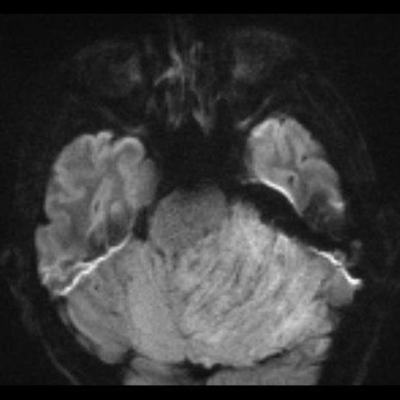

24 yaş, E

Baş ağrısı

Lhermitte duclos

Lhermitte-Duclos hastalığı (Dysplastic cerebellar gangliocytoma)

Dysplastic cerebellar gangliocytoma(Lhermitte-Duclos hastalığı)

Lhermitte-Duclos hastalığı

Displastik serebellar gangliositoma